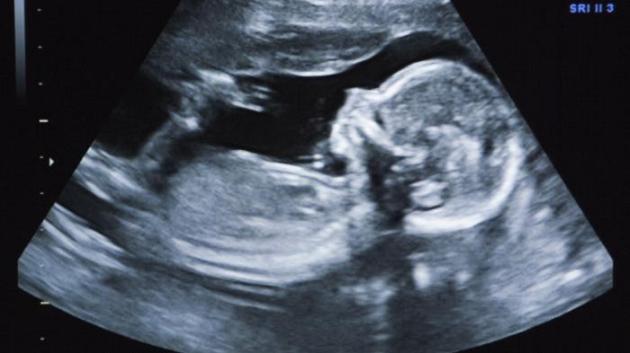

Santiago du Chili, Chili | AFP | samedi 20/06/2015 - Des examens de routine après une chute ont révélé qu'une grand-mère chilienne de 92 ans portait un foetus momifié pesant près de deux kilos depuis au moins 50 ans, ont révélé vendredi des sources médicales.

C'est lors d'une radiographie des hanches que le fœtus, qui avait un développement d'environ sept mois et pesait deux kilos a été découvert.

Pour des raisons non précisées, le fœtus s'est momifié sans causer de gêne particulière, la femme ignorant à l'époque qu'elle était enceinte.